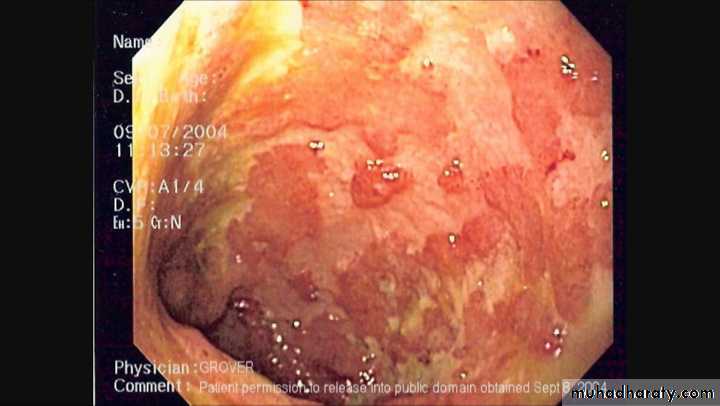

ULCERATIVE COLITIS

Colonic inflammation is diffuse,confluent and superficial, primarily affecting the mucosa and sub mucosa.Chronic mucosal ulceration is associated with formation of granulation tissue and regeneration ,leading to a polyp like pseudopolyposis,

Structuring in UC is very unusual and urgent assessment because of the possibility of coexisting carcinoma.A small proportion of patients with colonic dysplasia may develop irregular mucosal swelling (dysplasia-associated lesions,DALMs),highly predictive of coexisting of carcinoma.

Histological examination reveals inflammatory cells in lamina propria,walls of crypts,and there are crypt abscesses.There is depletion of goblet cell mucin .

Endoscopy and biopsy by sigmoidoscopy or colonoscopy.